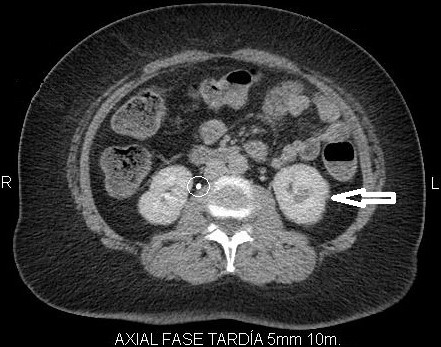

Fase excretora o arterial tardía

Comienza aproximadamente a los 3 minutos posteriores a la inyección del medio de contraste y permite evaluar su excreción por el sistema colector; por lo tanto, es útil para evaluar la relación de la masa con los cálices y la pelvis renal y llegar a una mejor planificación quirúrgica conservadora en un caso dado 3-4 (Fig. 4).